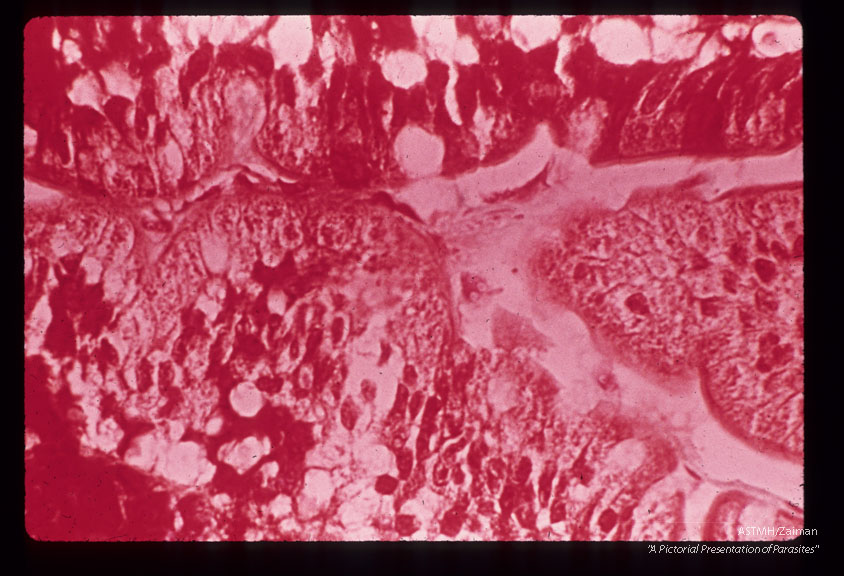

Trichrome stained peroral biopsy of duodenum showing trophozoites in close proximity to mucosa.

Giardia lamblia

Description: Trichrome stained peroral biopsy of duodenum showing trophozoites in close proximity to mucosa.